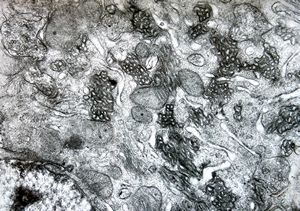

M,5y. | mitochondrial changes - Reye hepatocerebral syndrome